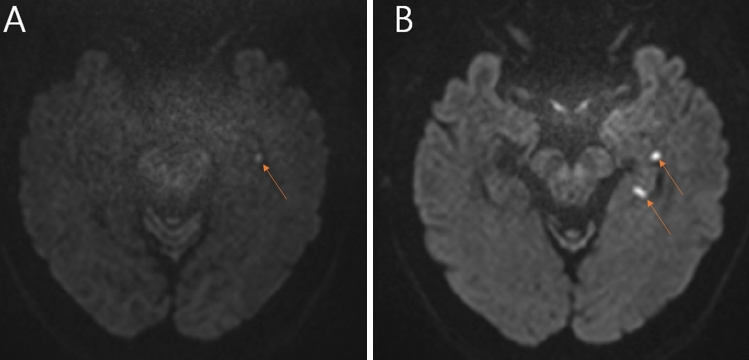

Results: Dizziness was reported in 30.6% (19/62 episodes), and spatial disorientation in 25.0% (16/64 episodes). In multivariable analysis, dizziness was independently associated with headache [odds ratio (OR) = 6.94; 95% confidence interval (CI) 1.91-25.25; p = 0.003] and Valsalva-like provoking events (OR = 4.19; 95% CI 1.14-15.38; p = 0.031). Abnormalities in ocular vestibular-evoked myogenic potentials (VEMPs) were significantly association with dizziness in univariate analysis (OR = 4.00; 95% CI 1.13-14.09; p = 0.031), but not in the multivariable analysis. In relation to spatial disorientation, abnormal cervical VEMPs showed a significant difference in chi-square test (p = 0.043), and a trend toward association in multivariable analysis (OR = 3.28; 95% CI 0.885-12.19; p = 0.076), suggesting otolithic vestibular dysfunction. There was a trend-level association between spatial disorientation and lower Korea-Montreal Cognitive Assessment scores (p = 0.066). Interestingly, patients in the spatial disorientation group showed better performance in visual memory immediate recall (p = 0.061), although this did not reach statistical significance. Hippocampal lesions were identified in 75.0% of TGA episodes, most commonly involving the hippocampal head. However, lesion laterality (left, right, or bilateral) was not associated with dizziness, spatial disorientation, or vestibular abnormalities.